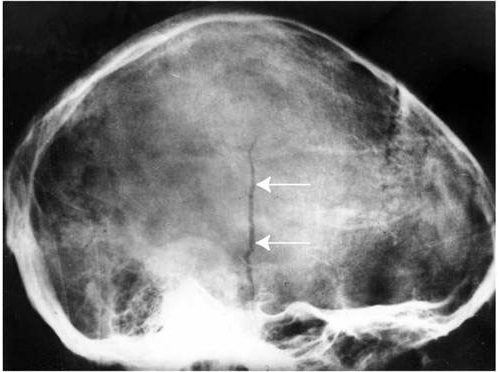

- Краниографию — метод рентгеновского исследования, не требующий введения контрастного вещества.